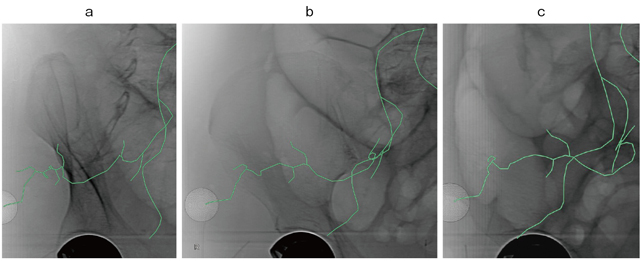

図2 working angleの術前シミュレーション

a:RAO38° b:正面像 c:LAO26° 右上殿動脈遠位からの出血症例。

任意の角度に回転したときの血管走行と病変位置を把握できる。